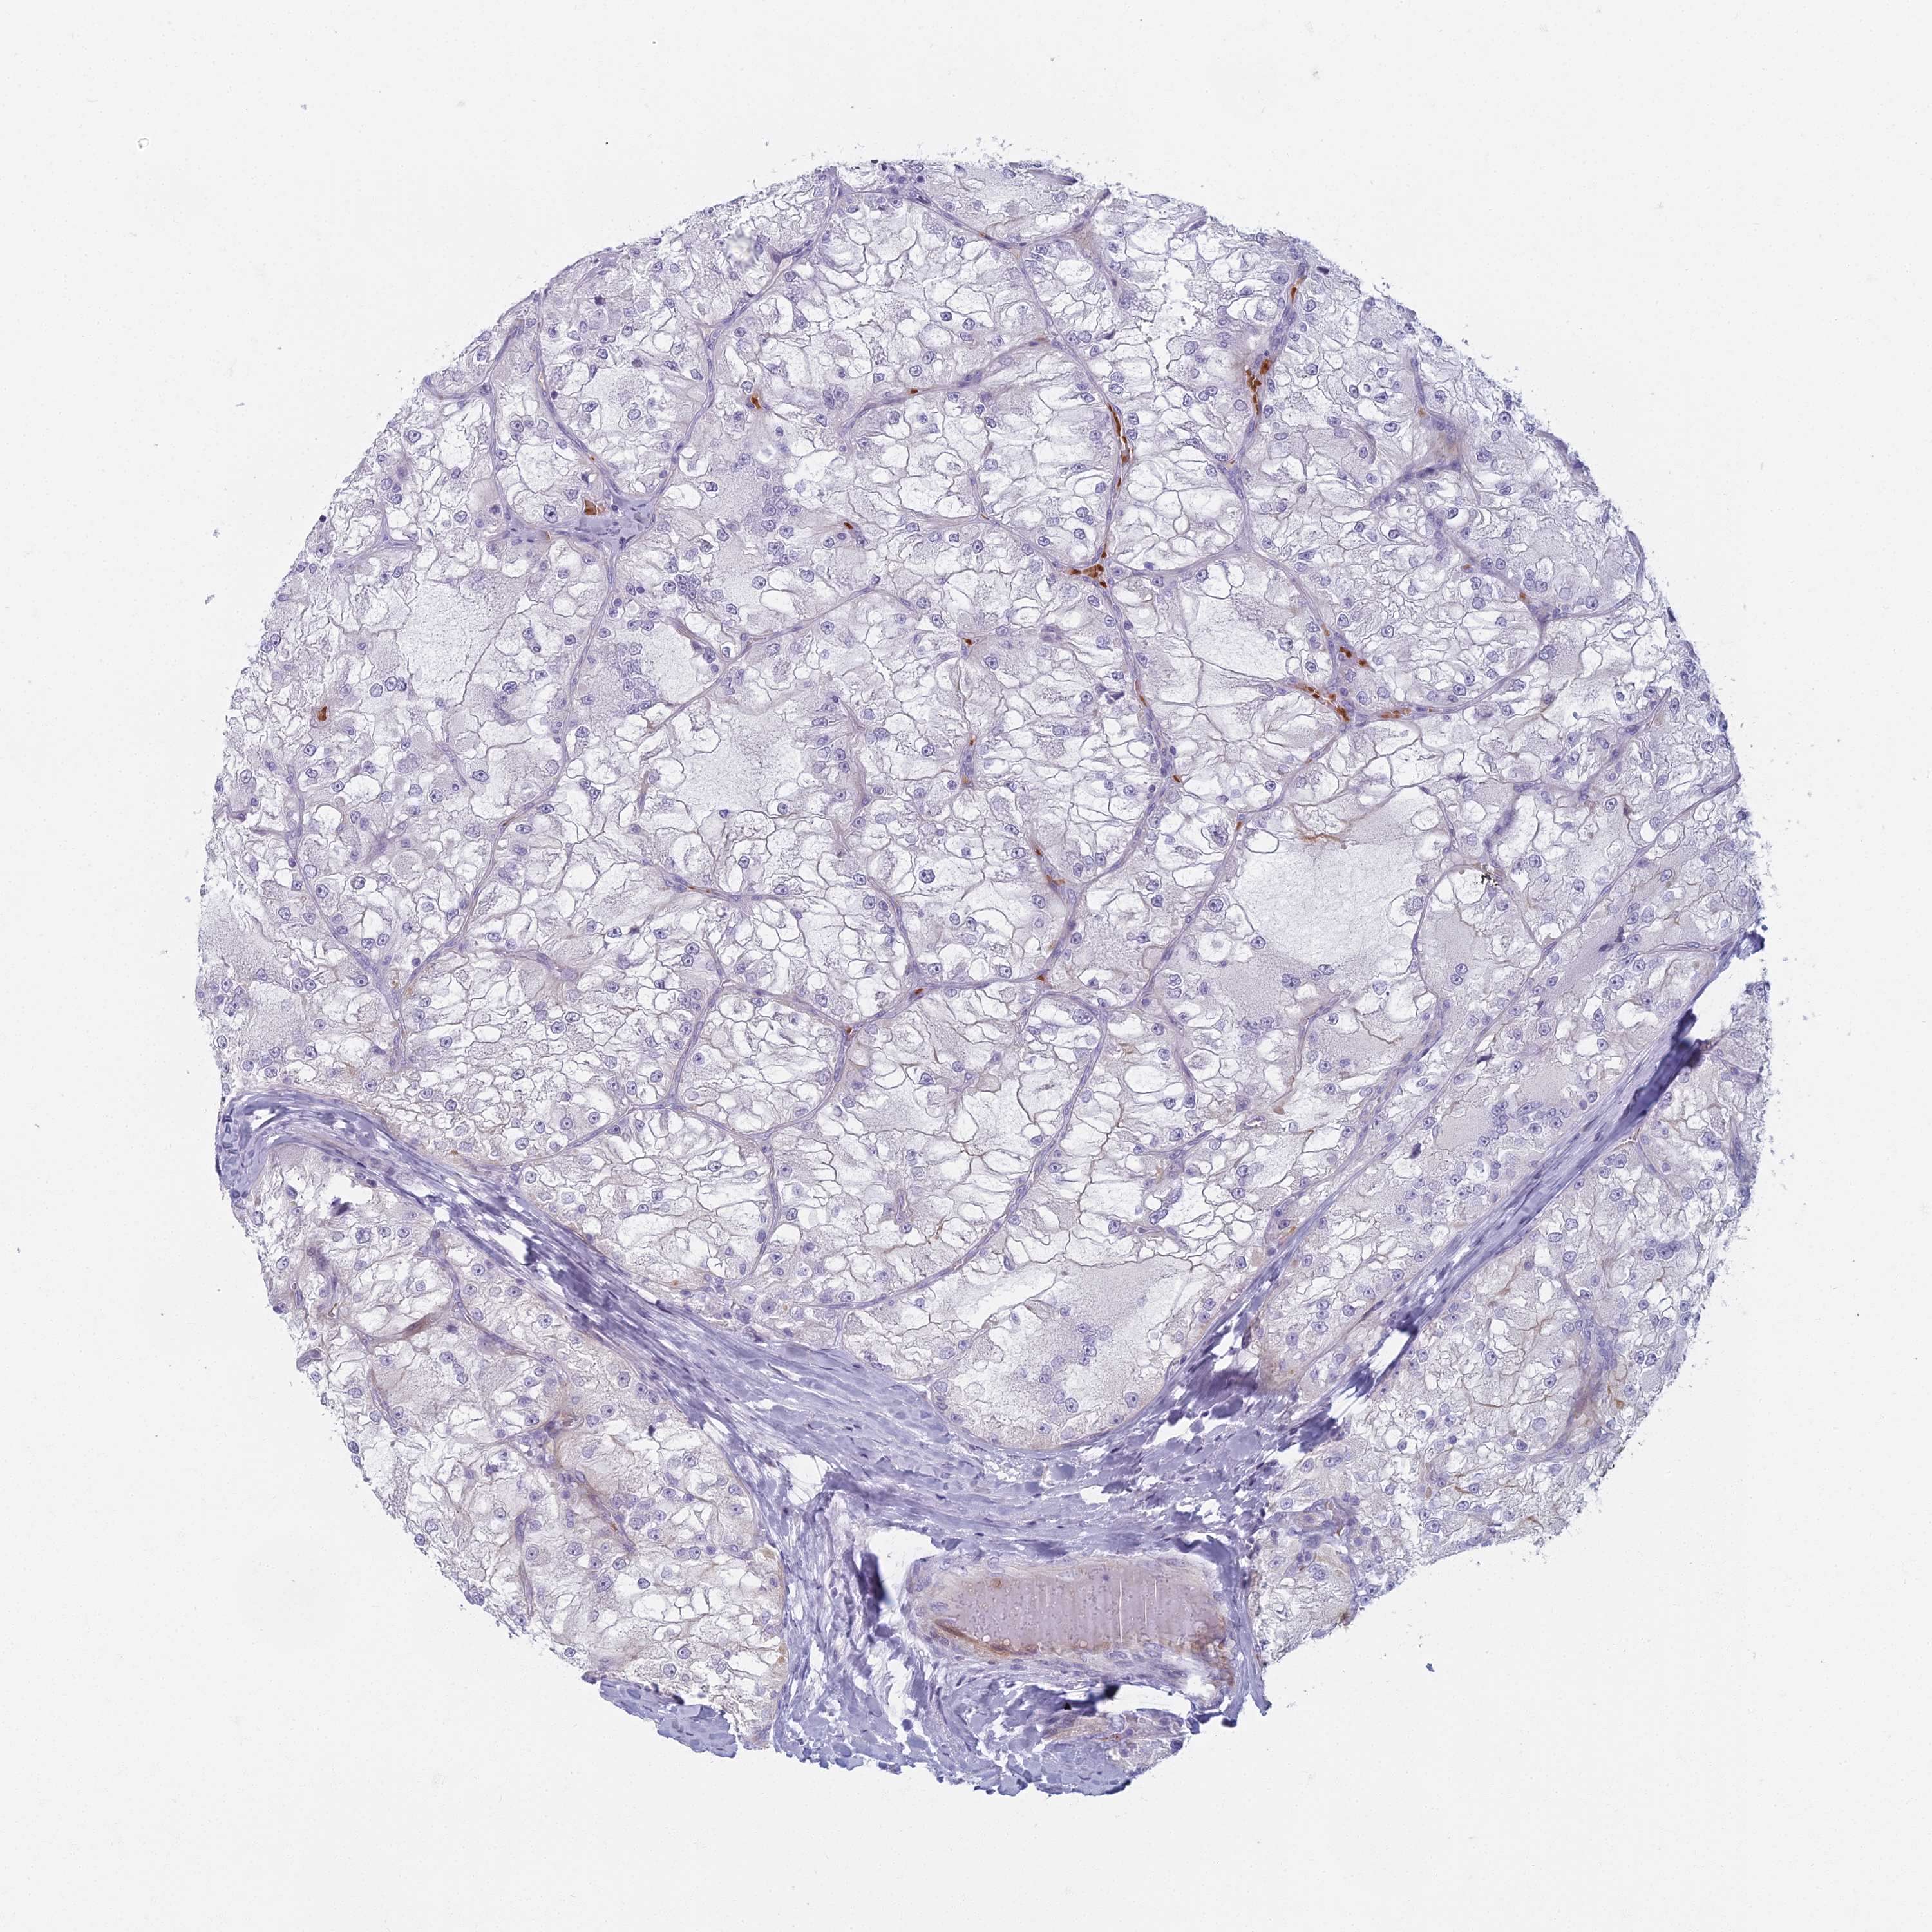

TCGA-GL-8500-01A 63 years, male, white, stage:Stage I, alive, 841 days 6.3

TCGA-A4-7585-01A 67 years, male, white, stage:Stage III, dead, 1070 days 6.2

TCGA-B3-8121-01A 48 years, female, black or african american, stage:Stage I, alive, 379 days 6.2

TCGA-SX-A71U-01A 57 years, male, white, stage:Stage I, alive, 1357 days 6.2